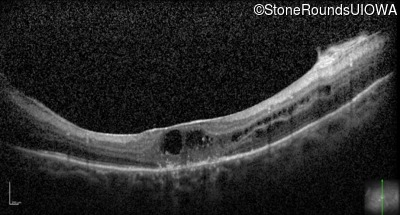

Optical Coherence Tomography - Right - 20/50 +2

Exemplar / OCT Stack